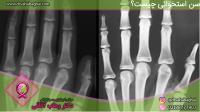

اشعه ایکس

اشعه ایکس یا رادیوگرافی ساده معمولاً به منظور مشاهده بافت‌های سخت و استخوانی استفاده می‌شود. در تصاویر بدست آمده از رادیوگرافی ساده، استخوان‌ها و بافت‌های سخت‌تر به رنگ سفید و با کنتراست بالا نسبت به پس زمینه تیره نمایش داده می‌شوند. بسیاری از بافت‌های دیگر بدن به صورت طیف‌های خاکستری رنگ در این تصاویر مشاهده می‌شوند. از رادیوگرافی ساده بیشتر به منظور تشخیص شکستگی‌های استخوان و انسداد در مجاری ادراری استفاده می‌شود. با این حال، رادیوگرافی از قفسه سینه گاهی می‌تواند وجود سرطان ریه در بیمار را تشخیص دهد. یکی دیگر از کاربردهای اشعه ایکس در رادیوگرافی، تشخیص بیماری های فک و دندان است.